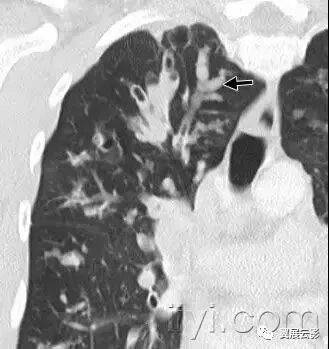

十八、小叶中心性:

解剖:小叶中心性用于描述次级肺小叶的支气管血管束中心区域。病理学上也用这一术语描述终末小支气管远端,位于呼吸性细支气管和肺泡管中心的病变。

CT:正常次级肺小叶中心的点状或者线状的密度增高影,胸膜下25px范围内最明显,代表小叶内的动脉,直径约1mm。

小叶中心性异常包括(1)结节(2)树芽征,提示小气道病变(3)由于临近间质的增厚或者浸润导致小叶中心结果更加清晰(4)小叶中心性肺气肿导致的异常低密度。

附图为小叶中心性肺气肿